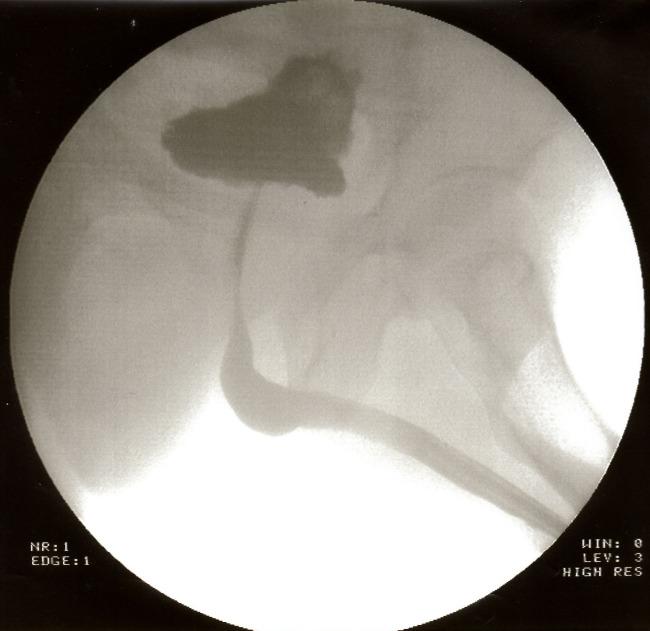

For bulbar urethral strictures up to 2.5 cm in length, the one-stage urethral plastic surgery with stricture excision and direct end-to-end anastomosis remains the best procedure to guarantee a high success rate. This retrospective review shows the results of 21 patients who underwent bulbar end-to-end anastomosis from 2010-2013. In 20 cases (95.3%) good results were archived. The criteria of success were identified by pre- and postoperative radiological diagnostics and uroflowmetry.